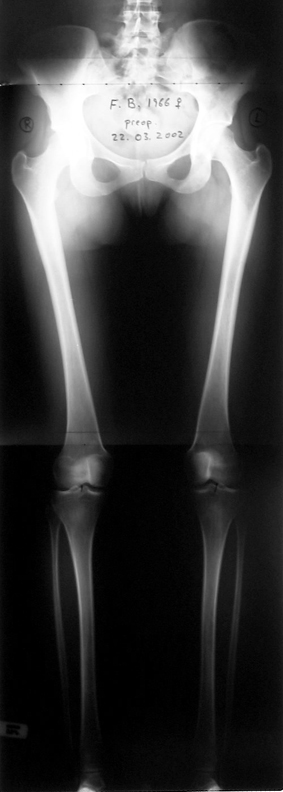

Lower limb length discrepancy is more than just a cosmetic problem; it leads to functional orthopedic problems. Orthopedic surgeons are very interested in the treatment of this pathological condition because imbalance at the frontal plane causes changes in walking pattern, and it also causes degenerative changes at the axial skeleton.

In selected cases, we prefer to use a combination of a unilateral dynamic axial fixator and an interlocked intramedullary nail, in order to protect the length and alignment after the completion of the lengthening procedure. As a prerequisite for this technique, the narowest diameter of the medullary cavity shall be wider than 7 mm and the length of the nail segment distal to the osteotomy site shall be at least 8 cm. after the completion of the lengthening procedure.The intramedullary nail neutralizes shear and bending forces on femur during lengthening, shortens external fixation time, and protects newly formed bone against fractures. In our series, subtrochanteric osteotomy was performed in one case. No varus angulation occured despite the intramedullary nail.

Despite low sample size, our aim was to compare two groups with matching ethiology, age, location and amount of the deformity and other similar factors. We neglected simultaneous tibial lengthening and osteotomy site in this preliminary study. The sample size was not enough to conduct a prospective randomized trial. Although the results of the study did not produce statistically significant data, it is the first and only example in our country and conveys significant experience.